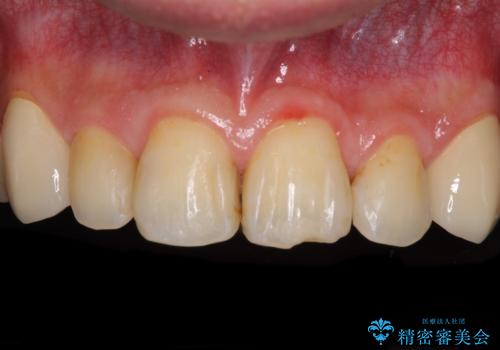

- 以前矯正を行った際に前歯が虫歯だらけとなり、審美面を気にして来院された患者様です。

虫歯の大きかった左右犬歯はオールセラミッククラウンで補綴治療をおこない、4前歯は研磨や古い充填物の詰め直しを行いました。

歯並びは良くなったものの、着色が気になって口元を見せることを躊躇していた用ですが、治療後は他人の視線を気にすることがなくなったようで、大変満足していただきました。